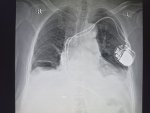

Гидрач слева и множественные очаги

>>327474800 (OP)

Аноним 09/12/25 Втр 09:15:47 #88 №327476565

Бля друг у нас ровно 1 рентген снимок в прямой проекции. Нам надо дать "диагноз" с описанием, чтобы мы тут друг друга все поняли. Как ещё сказать что патология на снимке внизу лёгких?